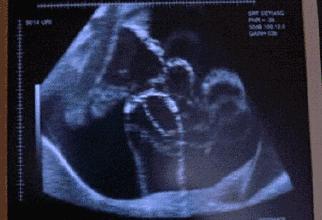

胎动,就是胎儿在子宫里的活动。最开始,因为宝宝还太小,所以妈妈们很难感受到。但是在18-20周之间,宝宝的手脚能够触碰到子宫壁,这时很多孕妈就能够感受到明显的胎动了。